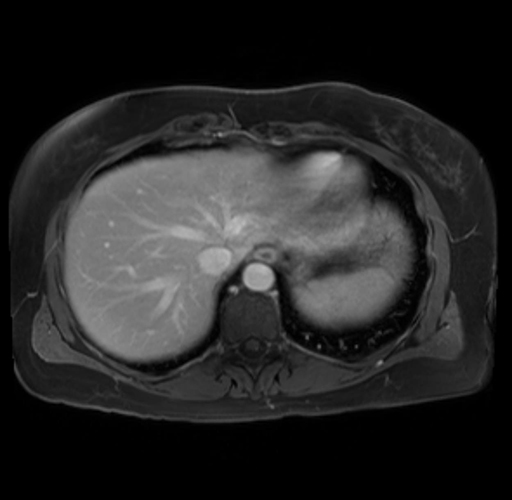

Imaging Analysis

Look through the patient's CT scan to identify any areas of concern for the necessary procedure.

Based on your CT findings, which issue(s) are present and would give reason for "planned slowing down moment(s)" in this case?